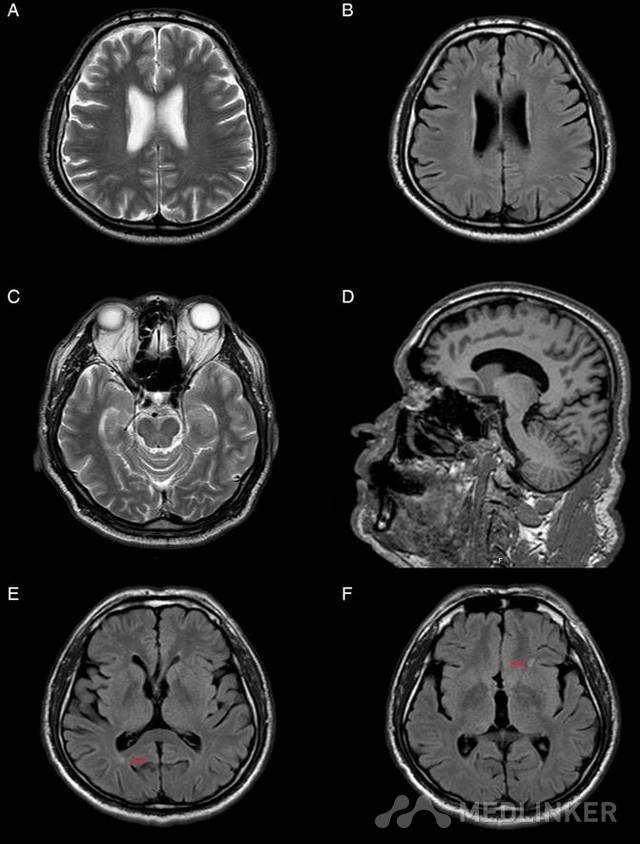

本文附有选择题,题目为:额叶痴呆的症状包括? 异常性行为怎么会与痴呆有关呢?近日BMJ Case Reports杂志就刊登了如下一则病例报道,介绍了一例因额叶痴呆导致性行为异常的病例,一起来学习下吧。 患者男性,55岁,职业教师,由其妻子带来精神病门诊就诊。检查期间,未表现出任何症状,并对自己的情况不甚了解。根据其妻子描述,患者近来使用社交网络如Facebook等的时间增加,并与不认识的女性通宵达旦地聊天。此间,患者对其妻子的性生活要求次数增加,并开始看色情类视频。 此前患者夫妻性生活频率是每周一至两次,现在患者出现频繁手淫,不管其妻子或其他任何人是否看到。其妻子发现这些情况与他的年龄不符并感到奇怪,故来就诊。患者及其妻子否认出现任何认知功能下降情况,且之前未有过精神病史。患者曾被诊断为阻塞性睡眠呼吸暂停综合征,并建议行连续气道正压治疗,但是患者并未接受该治疗。 目前考虑的鉴别诊断包括:双相情感障碍、精神分裂症、器质性精神病和老年痴呆症。完善精神科相关检查后,行头颅磁共振成像和量化脑电图(EEG)检查。脑MRI显示局灶性皮质萎缩和多胶质增生灶(图1);脑电图未发现阵发性活动(图2);MMSE评分为28/30;额叶行为检查(FBI)得分33(临界值为27)。 患者开始口服利培酮1.5mg/天、多奈哌齐10mg/天。随访期间,其去抑制症状次数减少,为防止其妻子崩溃,我们对其还进行了进一步的心理教育。3年后,患者FBI得分下降到了4分,MMSE评分下降到了27。 性欲亢进和异常性行为(ISB)可见于痴呆综合征患者,尤其是那些额颞叶痴呆(FTD)患者。性欲亢进和ISB并不伴有认知功能障碍可能 FTD出现的第一个征象,因此在表现为去抑制症状的患者中,需要评估脑MRI以排除FTD的鉴别诊断。 学习要点: 性欲亢进和异常性行为(ISB)可能是早期额叶痴呆的首发症状; MRI上出现额叶皮质脑萎缩对诊断有重要意义; ISB可服用利培酮和奥氮平联合治疗进行控制。 附图: 图1.(A,B 和 D)脑 MRI 显示双侧额叶萎缩。(C)颞叶是正常的。(E、F)部分额叶和枕叶胶质增生(红色箭头)。 图2. 定量脑电图中未见阵发性活动。